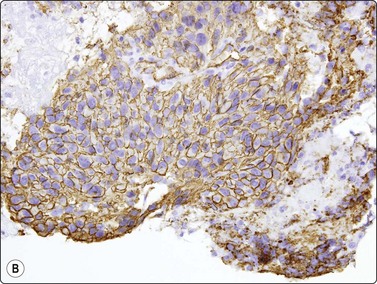

image image

Fig. 11.23 Gastrointestinal stromal tumor (GIST)

(A, B) Cell block sections stained for C-kit (CD117) and CD34 (A, C-kit, HP; B, CD34, HP).

Gastrointestinal stromal tumors (GISTs), formerly classified as smooth muscle tumors, have now been extracted as a distinct entity. They are mesenchymal tumors, arising in the wall of the gastrointestinal tract, showing a spectrum of benign, borderline and malignant behavior. They are typically spindled but there is also an epithelioid variant showing the same antigen profile. Cytodiagnosis of the spindle-celled variant is relatively simple, showing fascicles of spindled cells with elongated, cigar- or comma-shaped nuclei, often set in a wispy filamentous background (Fig. 11.22A and B). The epithelioid variant presents greater difficulty, resembling epithelial tumors. The cells are round, cytoplasm distinct with a perinuclear halo, and nuclei vesicular (Fig. 11.22C). The tumors express CD117 (C-kit) and CD34 (Figs 11.23 and 11.24), but are negative for desmin, S-100 and keratin. Cytopathologists must be ‘GIST-conscious’ owing to the responsiveness of these tumors to Gleevec, which can induce tumor regression and long-term response, even in metastases.132-136